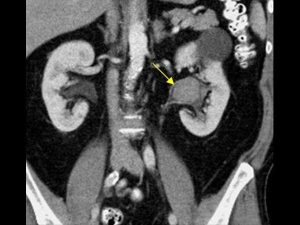

محل سنگ لگنچه کلیه در کلیه چپ

محل قرار گیری سنگ لگنچه کلیه در کلیه چپ

به ناحیه ای که در تصویر بالا Renal pelvis  نام گذاری شده است لگنچه کلیه می گویند. به سنگی که در ناحیه لگنچه کلیه قرار دارد سنگ لگنچه می گویند . معمولا روش های درمان سنگ لگنچه بر اساس سایز سنگ ها و جنس سنگ ها متفاوت می شود به همین جهت در این مقاله به توضیح روش دفع سنگ کلیه در لگنچه بر اساس اندازه سنگ لگنچه کلیه می پردازیم .